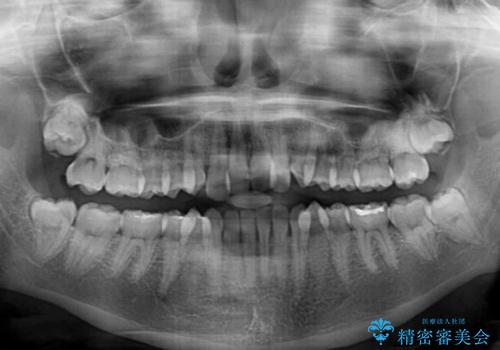

- 前歯のクロスバイトを治したいとのことで来院された患者様です。

できる限り楽して、短期間で治したいとのことで、ワイヤー装置にて矯正治療を行うこととしました。

- 症状により、抜歯が必要な場合があります